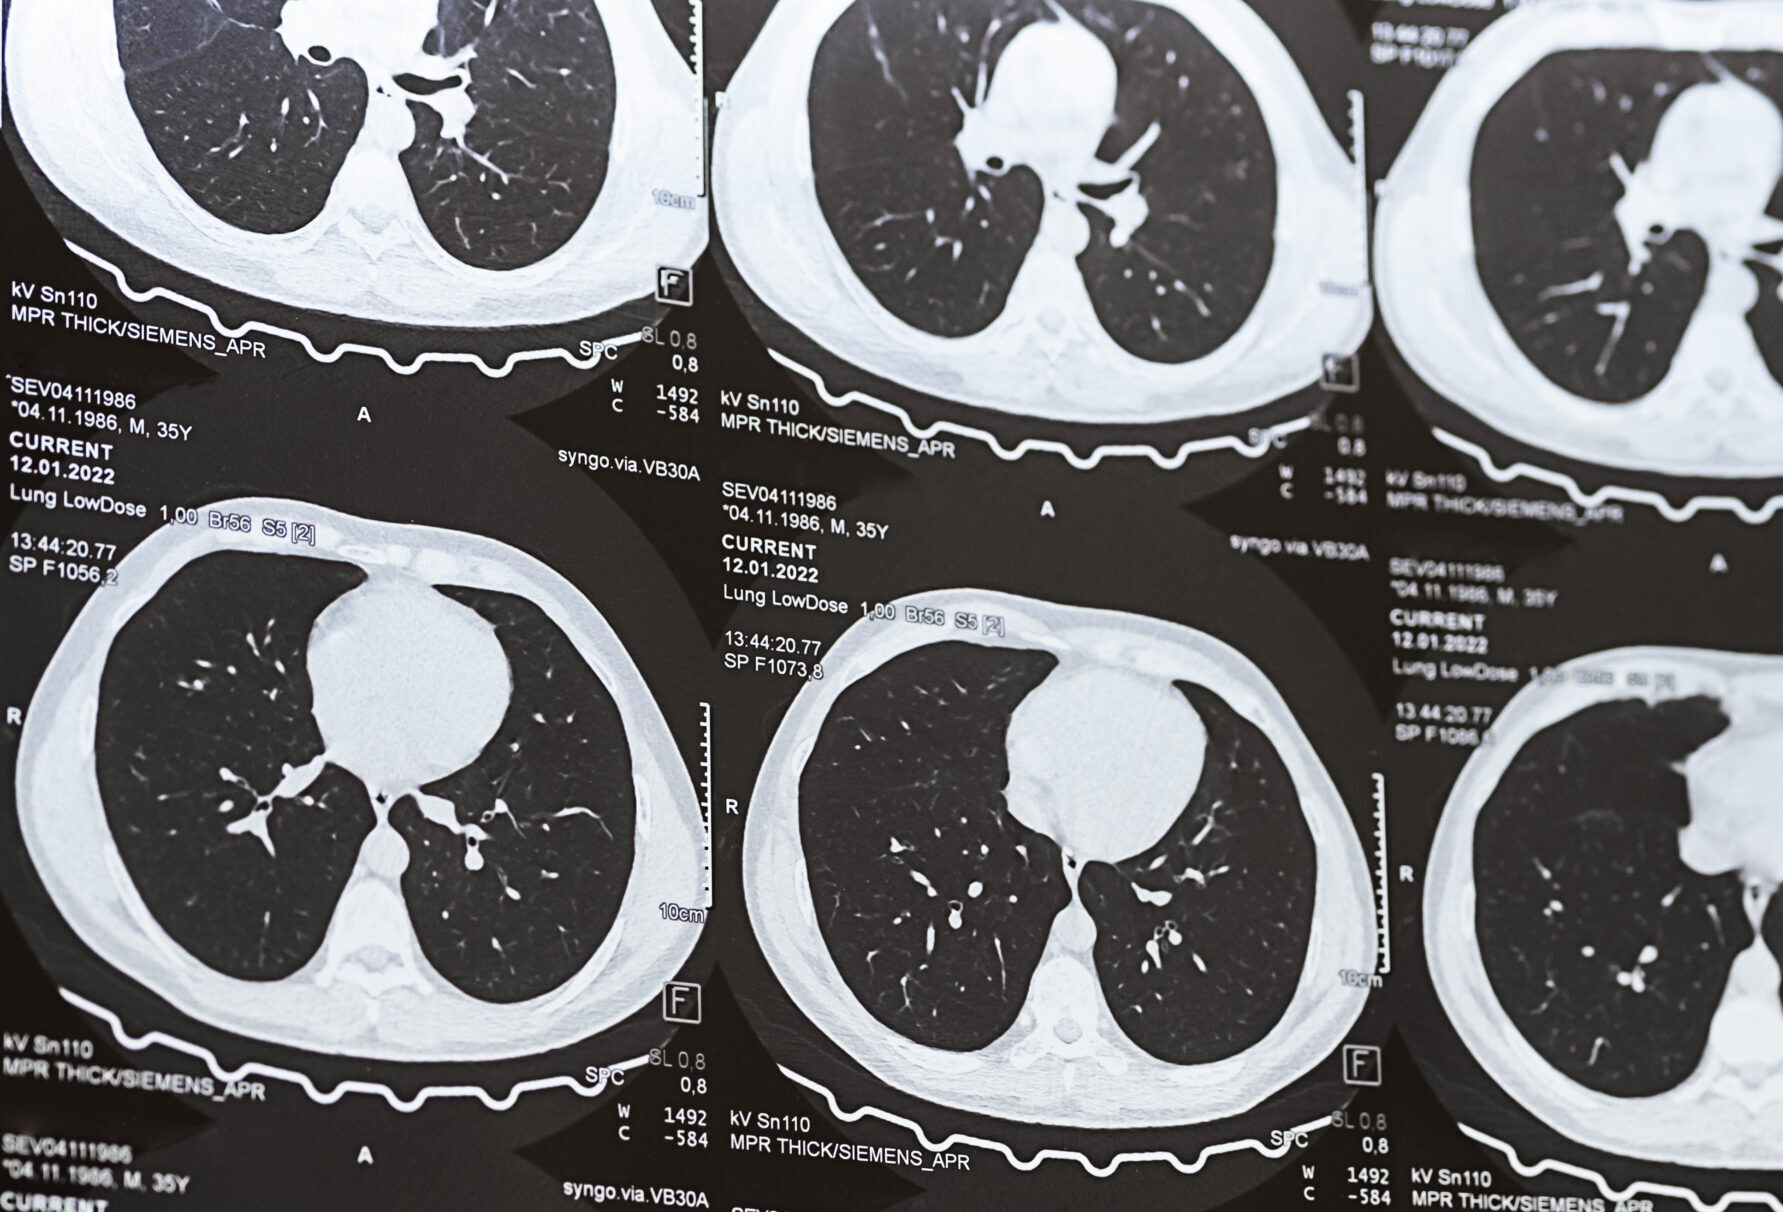

A CT lung screening uses low-dose computed tomography to produce detailed, three-dimensional images of the lungs. The scan is non-invasive, does not require a contrast injection, and is completed in just a few minutes. This approach allows us to evaluate and examine lung tissue carefully while keeping radiation exposure to a minimum.

You will lie on a motorized table that moves gently through the CT scanner. As the scanner rotates, it captures detailed images of your lungs in seconds. You may be asked to hold your breath briefly to ensure image clarity.

A board-certified radiologist carefully reviews the images, assessing lung tissue for nodules, structural changes, or other findings relevant to screening criteria.